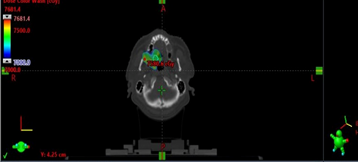

Postop histopathology of liver showing moderately differentiated hepatocellular carcinoma and Rectum showing moderately differentiated adenocarcinoma of rectum with free margins and free regional lymph nodes with perirectal tumor deposits pT3N1c. He received adjuvant external beam radiotherapy in view of T3 and node positive using Image guide radiotherapy (IGRT) to a dose of 45 Gy in 25 fractions to the post op bed and nodes in pelvis followed by 5.4 Gy in 3 fractions boost to the post-operative bed as shown in Figure 3 along with concurrent chemotherapy with oral capecitabine The patient received stereotactic body radiotherapy(SBRT) using CyberKnife to a dose of 30 Gy in 5 fractions to postop bed of liver using gold fiducial and synchrony respiratory tracking as shown in Figure 4. SBRT to liver considered in view of close margin 2mm.now on one and half year follow up whole body PET scan as shown in Figure 5 revealed no active disease and patient have a good quality of life.

Figure 3 Dose distribution of carcinoma rectum post-operative bed.